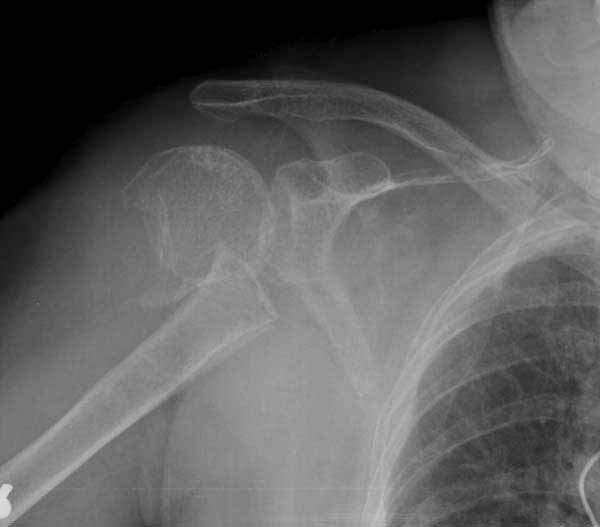

Набор мелких снимков не отражает истинную картину суставной поверхности лопатки, а также качество репозиции головки плеча. Необходимо доказать аксиальным снимком наличие покрытия головки. Правильная маркировка на рентген снимках и соответствие с выставленным диагнозом гарантирует от ошибок со стороной во время операции!

Здесь результат похожего случая, больная 87 лет, отягощенная сердечными делами и два года назад установка pacemaker и нескольких стентов. На третий день, сегодня утром сделали операцию. Послеоперационный псевдовывих связанный с релаксацией мышц и общим обезболиванием.